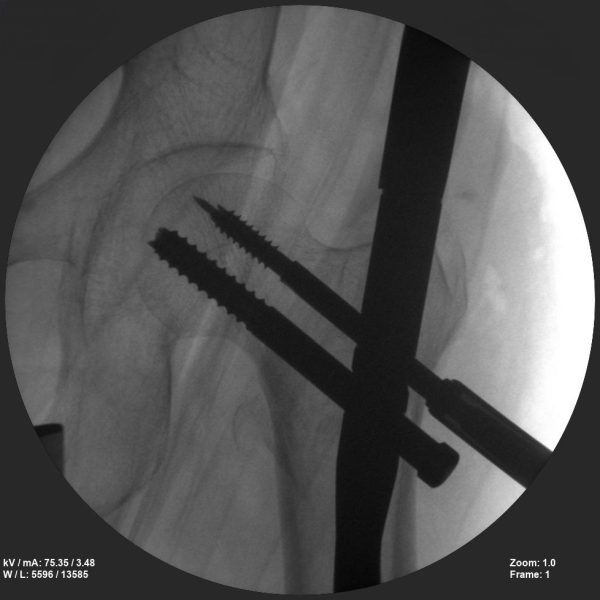

CRIF - Closed reduction internal fixation

ORIF - Open reduction internal fixation

Skan-C is a great C-arm for orthopaedic treatments for several reasons